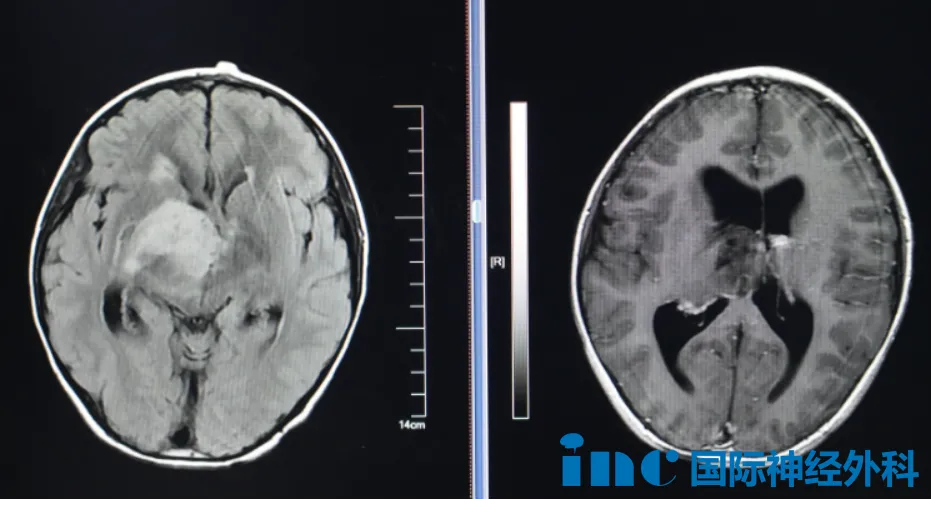

8岁男孩小航今年10月因外伤至当地医院检查头CT,意外发现右侧丘脑、基底节区占位、梗阻性脑积水。病灶大小约4.0cm×4.7cm×4.8cm,考虑弥漫中线胶质瘤可能大。患儿偶尔有记忆力下降,注意力不集中,喝水呛咳。

肿瘤如此之大,情况如此危急,下一步究竟该何去何从?巴特朗菲教授在评估后,给出了清晰而坚定的方向:孩子有明确手术指征,应尽快手术,不能再拖延。而对于这个胶质瘤,巴教授表示可能是低级别胶质瘤,但还是要看最终手术病理。这个评估让一直悬着心的父母,终于看到了希望的曙光。